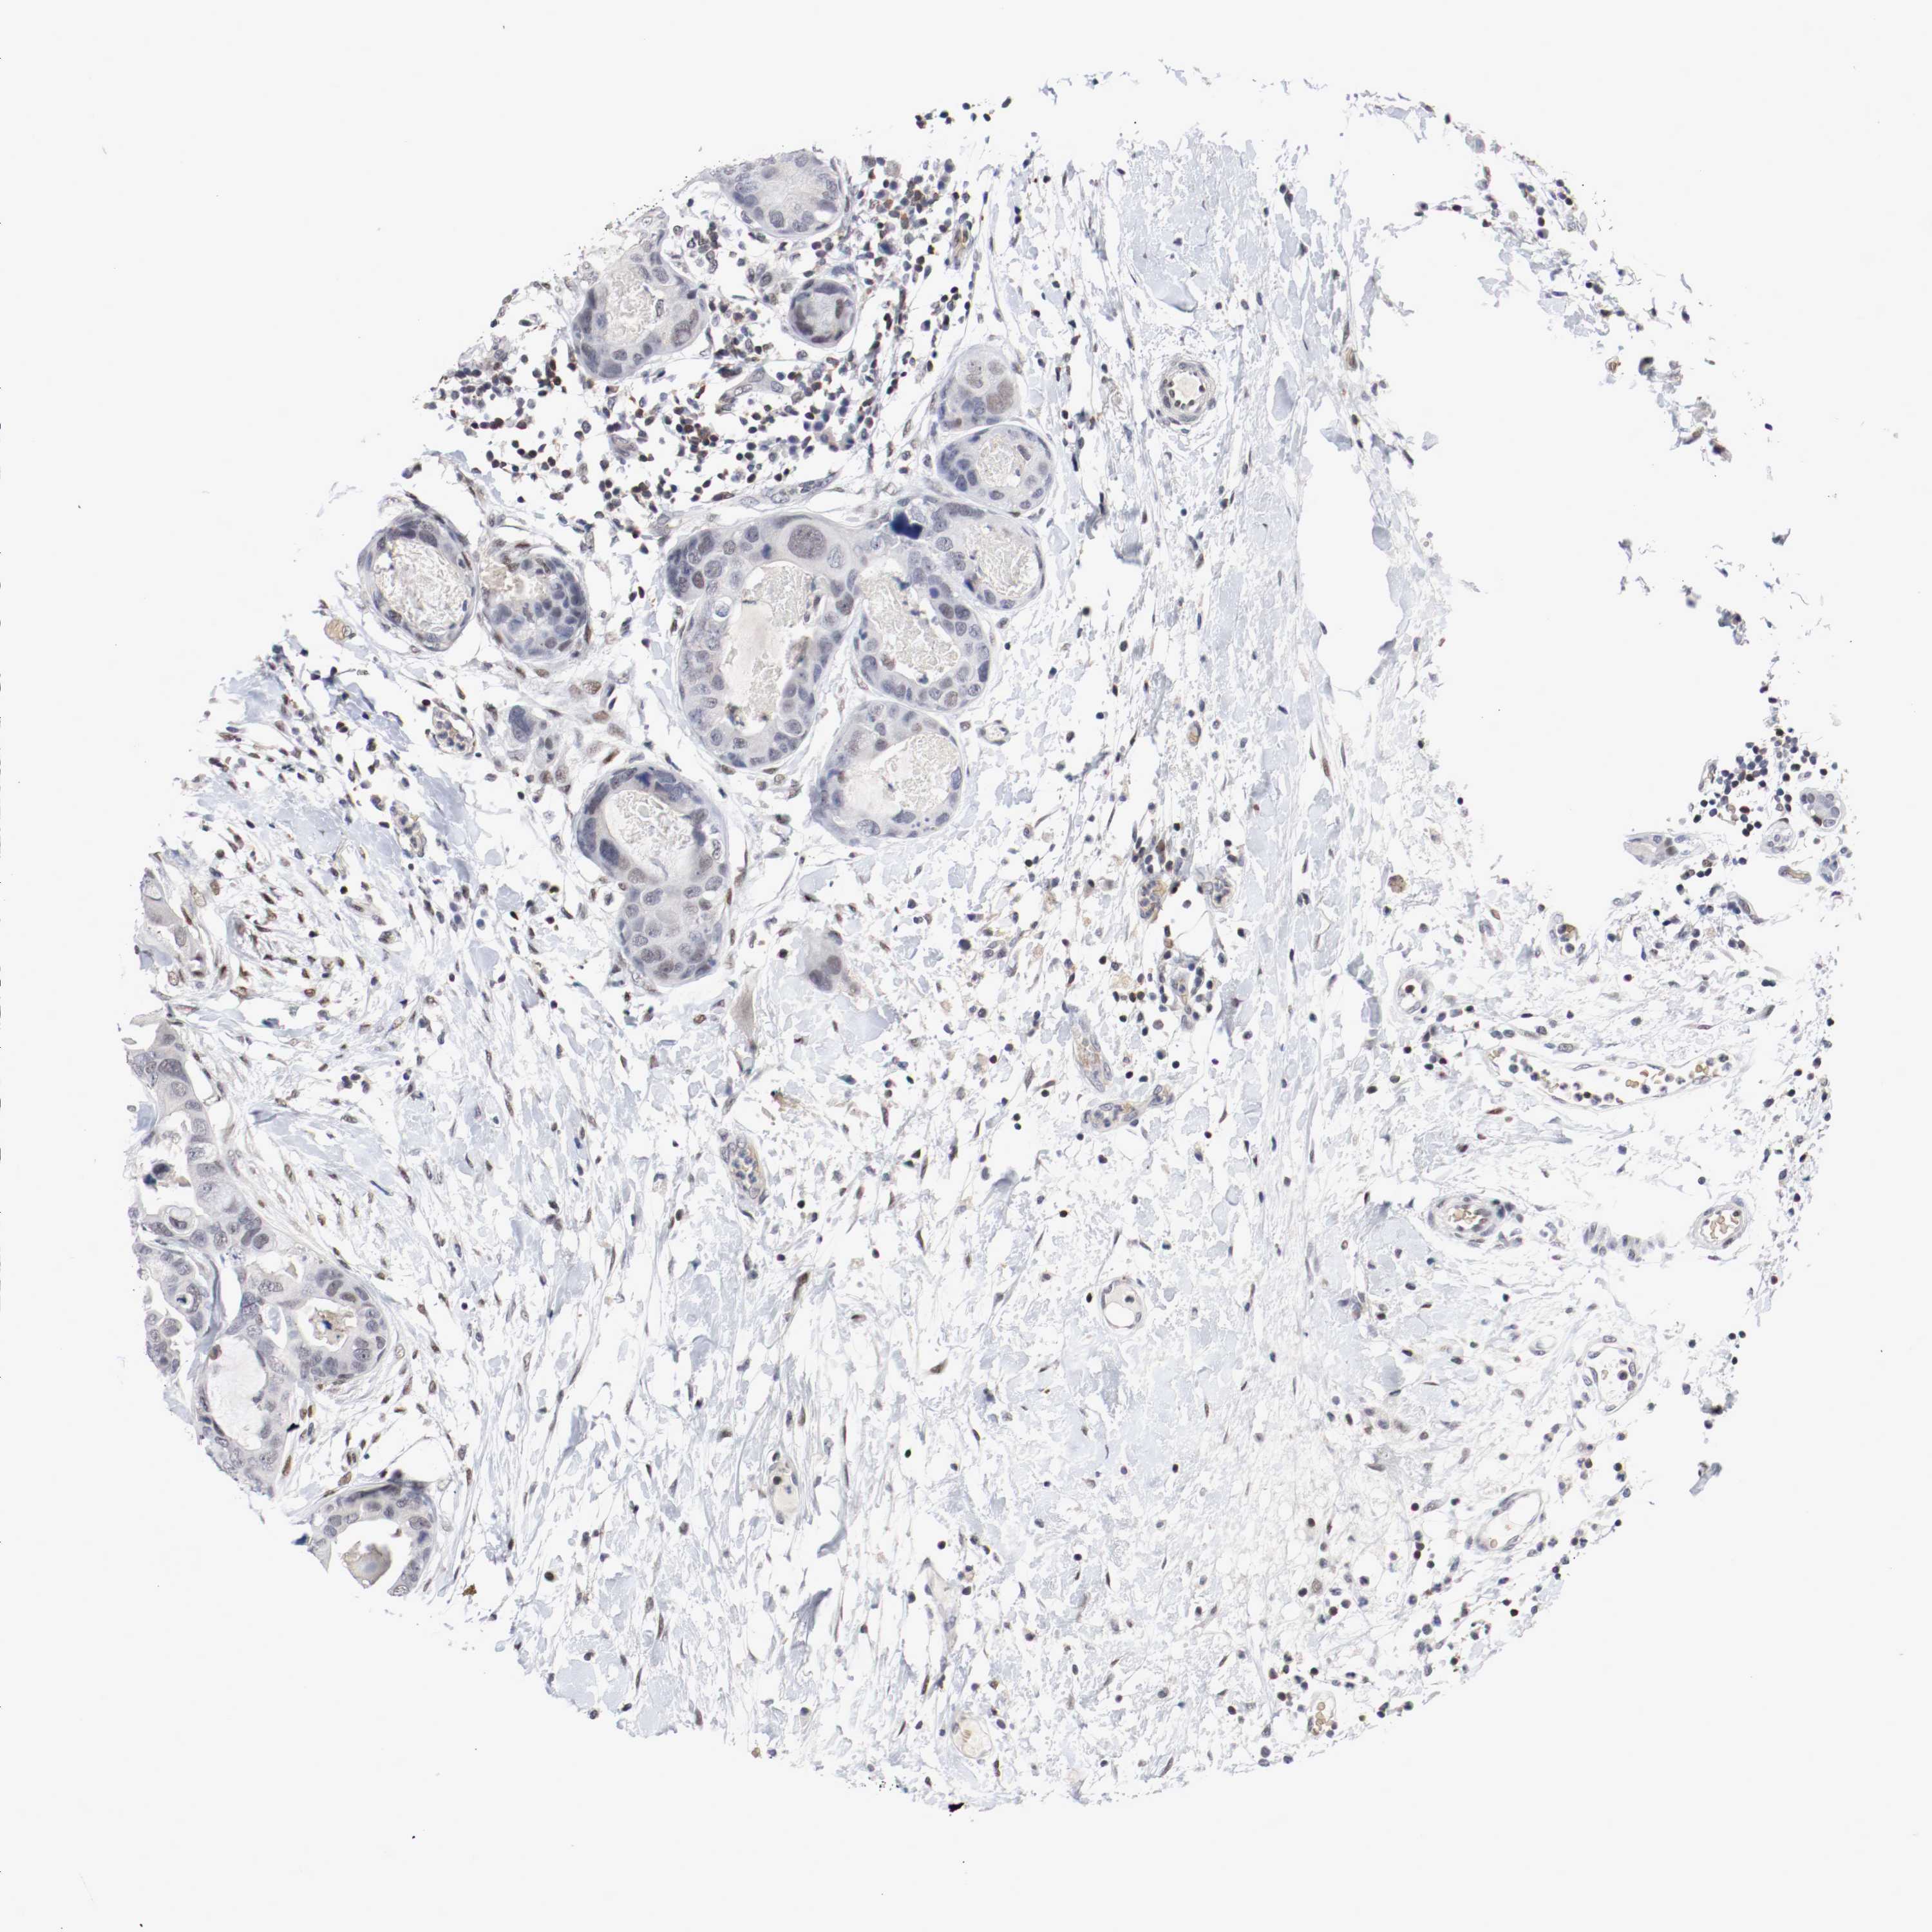

BRCA TCGA BRCA VALIDATION PROTEIN EXPRESSION